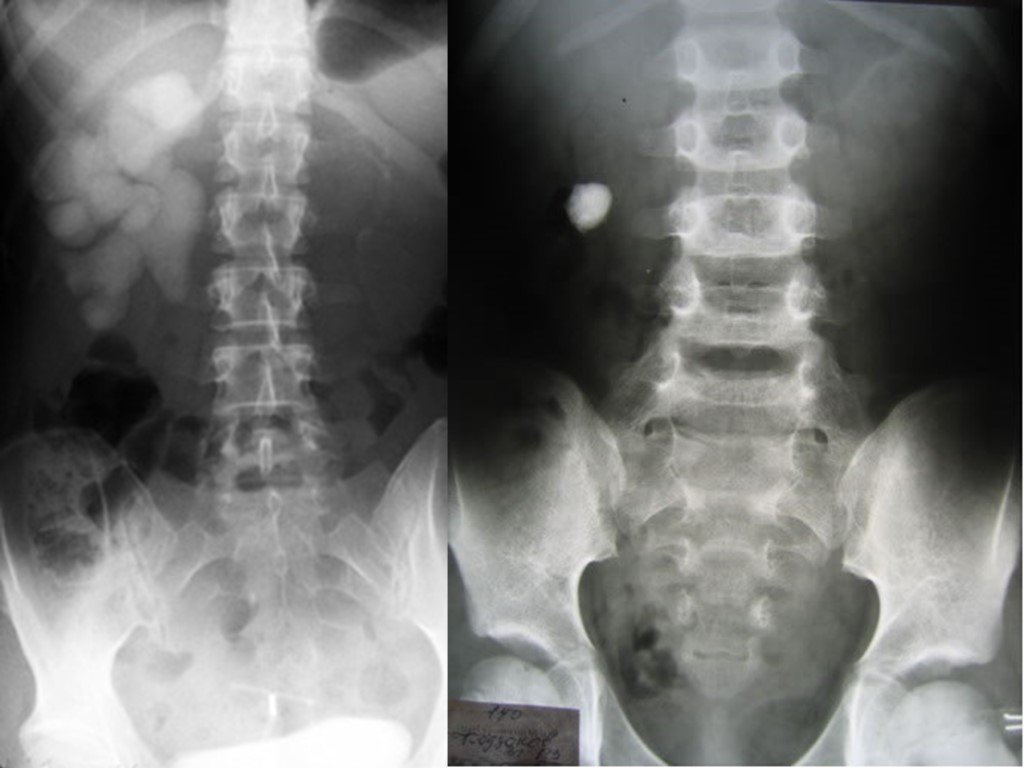

Медицинские изображения: Обзорная рентгенография урография

Раздел: Фокус на знании